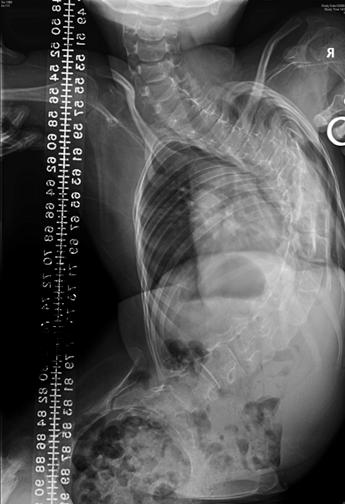

Neuromuscular scoliosis

![]() Fig. 4 Severe long thoracic curve in a girl suffering from spinal muscular atrophy. Note significant pelvic obliquity with poor sitting posture. |

![]() Fig. 5 Sitting AP radiograph of the same patient. Note how radiograph shows the true severity of the pelvic obliquity. This is best treated by surgery to allow comfortable seating. |